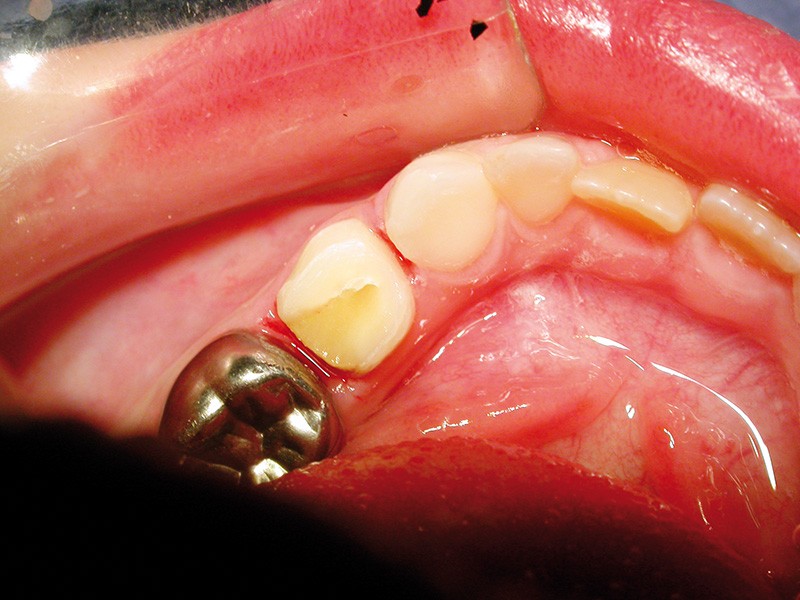

Les coiffes pédodontiques préformées (CPP) sont introduites en odontologie pédiatrique en 1950 par Humphrey. Ce sont des couronnes métalliques, en acier inoxydable, commercialisées par 3M qui ont la forme anatomique des molaires temporaires.

Les CPP représentent assez fidèlement l’anatomie idéale des couronnes des molaires temporaires. Présentées dans des coffrets assortis de plusieurs dimensions pour chaque dent temporaire, elles permettent de restaurer l’espace mésio-distal en rétablissant les points de contacts.

L’alliage inoxydable utilisé pour la fabrication des CPP est le nickel chrome. Cet alliage procure la résistance et l’élasticité de la coiffe.

L’élasticité du métal permet l’insertion de la coiffe et sa rétention. La ductilité offre un façonnage facile de la coiffe. L’épaisseur (2/10e de mm) et son poli permettent une bonne tolérance des tissus de soutien et une faible rétention de la plaque bactérienne.

Limites de la CPP : inesthétique

En dépit de toutes les qualités mentionnées auparavant, les CPP des molaires temporaires ont un inconvénient majeur : elles sont inesthétiques car métalliques.